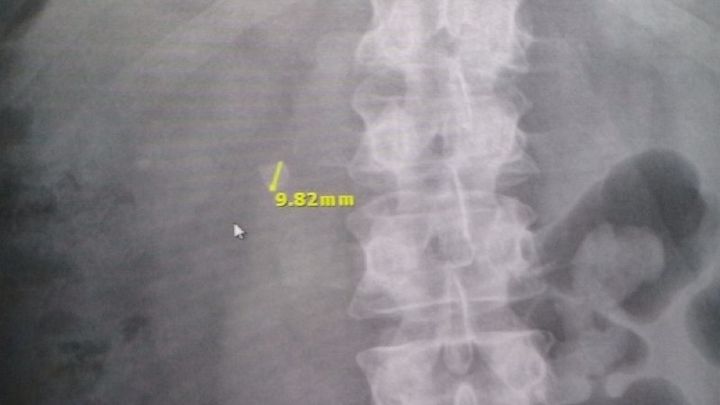

I need surgery to have a 9.82mm and two 2mm kidney stones removed from my right kidney. The surgery is set to take place on 12-1-15 at 4pm. However, my insurance will not cover any of the costs.

Pictured below is the 9.82mm stone. This is not a passable stone and will have to be broken up to pass.